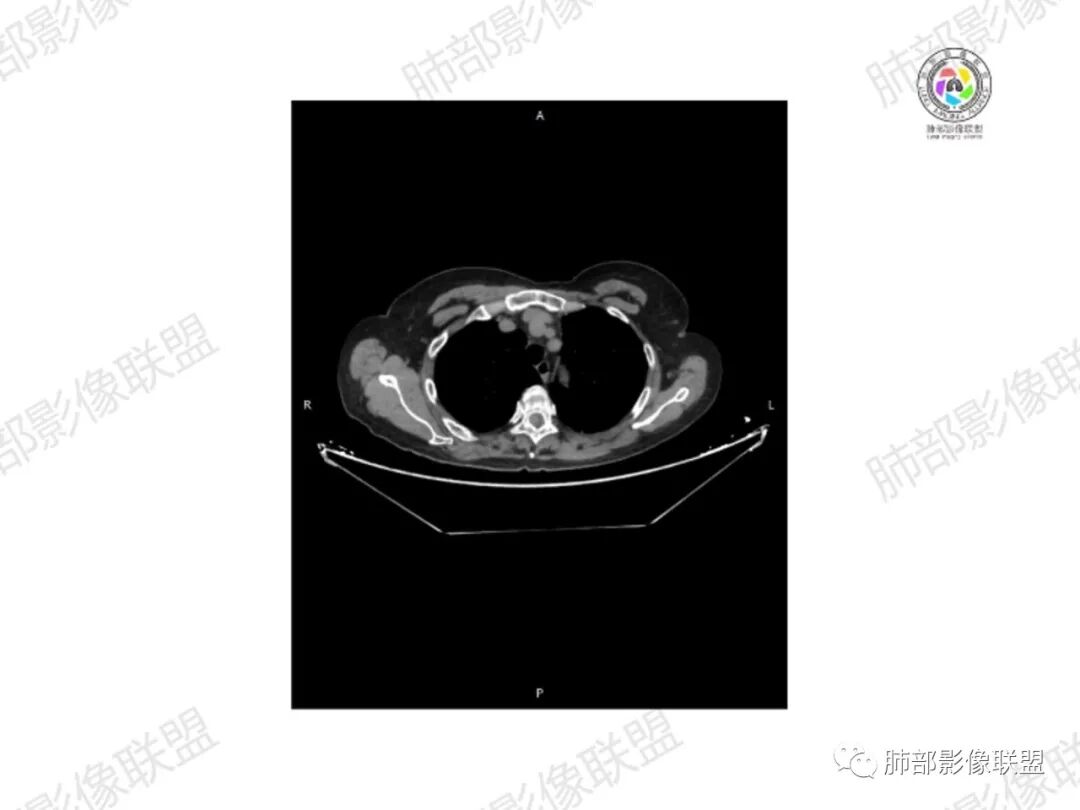

5.双肺多发类圆形结节影,边界清楚,随机分布,其间多见钙化密度影。

6.双肺门及纵隔未见肿大淋巴结。

3.双肺病灶符合转移瘤,伴有中央部分钙化者也以骨肉瘤转移较为多见。